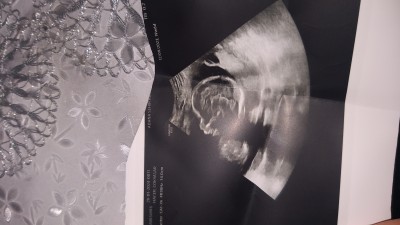

Kızlar 2defa aynı cinsiyet denildi sizler ne diyeceksiniz cinsiyet tahmini varmı

Resim yan döndü

Gebelik haftası 20

Kafasında pipisi yok kız bence..Allah akl fikr versn

Bebeğin kafa var bu ultrason da cinsiyet nasıl anlaşılır arkadaşım

Kız sadece kafaya bakarak nasıl bir tahminde bulunabiliriz:)